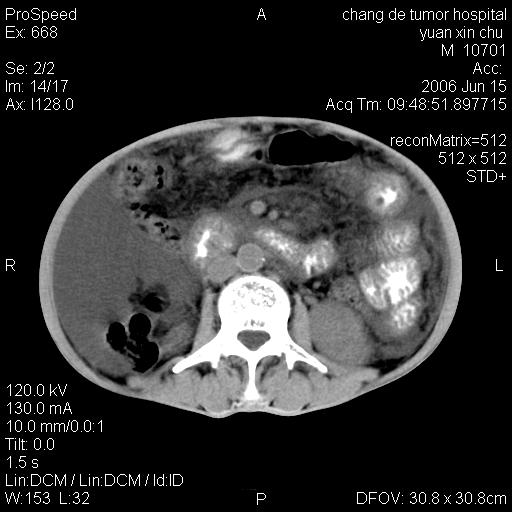

以下是引用qian在2007-4-23 19:06:00的发言:[br]胰腺体积增大,轮廓欠规则,肝轮廓波浪状改变,肝裂增宽,肝周、脾周有液性密度,腹膜后肿大淋巴结,考虑1、胰腺癌伴腹膜后淋巴结转移;2、肝硬化伴腹水。

以下是引用卜一在2007-4-23 20:12:00的发言:[br]胰腺体积增大,轮廓欠规则,肝轮廓波浪状改变,肝裂增宽,肝周、脾周有液性密度,腹膜后肿大淋巴结,考虑1、胰腺癌伴腹膜后淋巴结转移;2、肝硬化伴腹水。支持!